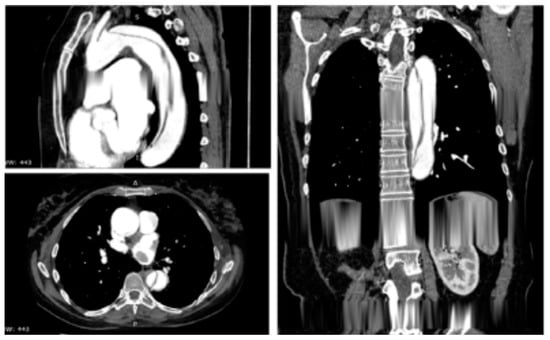

- Mauro, C.; Vriz, O.; Romano, L.; Citro, R.; Russo, V.; Ranieri, B.; Alamro, B.; Aladmawi, M.; Granata, R.; Galzerano, D.; et al. Imaging Cardiovascular Emergencies: Real World Clinical Cases. Heart Fail. Clin. 2020, 16, 331–346. [Google Scholar] [CrossRef] [PubMed]